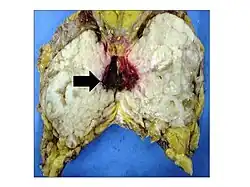

Phyllodes tumors may be considered benign, borderline, or malignant depending upon their histological features, including stromal cellularity, infiltration of the epithelial-stromal interface, and mitotic activity.[15] Due to their propensity to metastasize and grow quickly, almost all phyllodes tumors are regarded as having malignant potential and treated accordingly.[15] A large case series from the MD Anderson Cancer Center reported the incidence of each type of phyllodes tumor as benign (58%), borderline (12%), and malignant (30%).[16]

.jpg)

Malignant phyllodes tumors can behave similarly to sarcomas leading to development of blood-borne metastases.[16] Approximately 10% of phyllodes tumor develop distant metastases and this occurrence is higher (20%) in patients with histological-identified malignant tumors.[16] The most common site for distant metastases include the lung, bone, and abdominal viscera.[17] In more insidious cases, the parotid region has also been described in literature.[18]